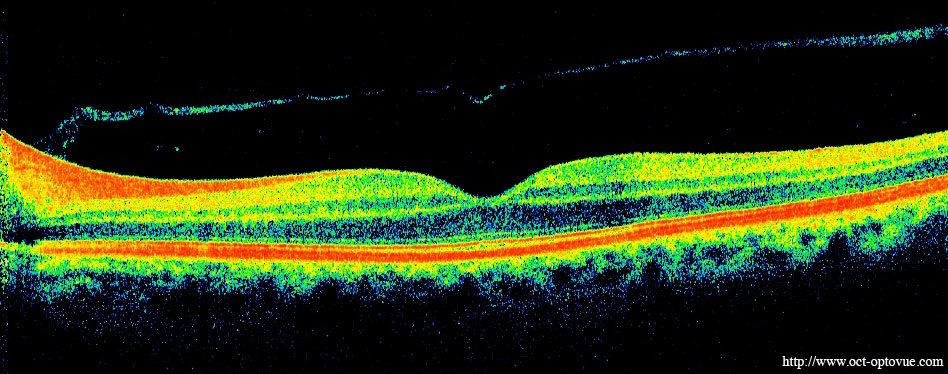

We also use optical coherence tomography (OCT), an imaging technique that uses infrared light reflections off the retina to genrate a cross-sectional view of the retinal tissue. These images can show evidence of AMD and thinning of the retina caused by cell death associated with AMD. This is what an OCT image looks like:

OCT image